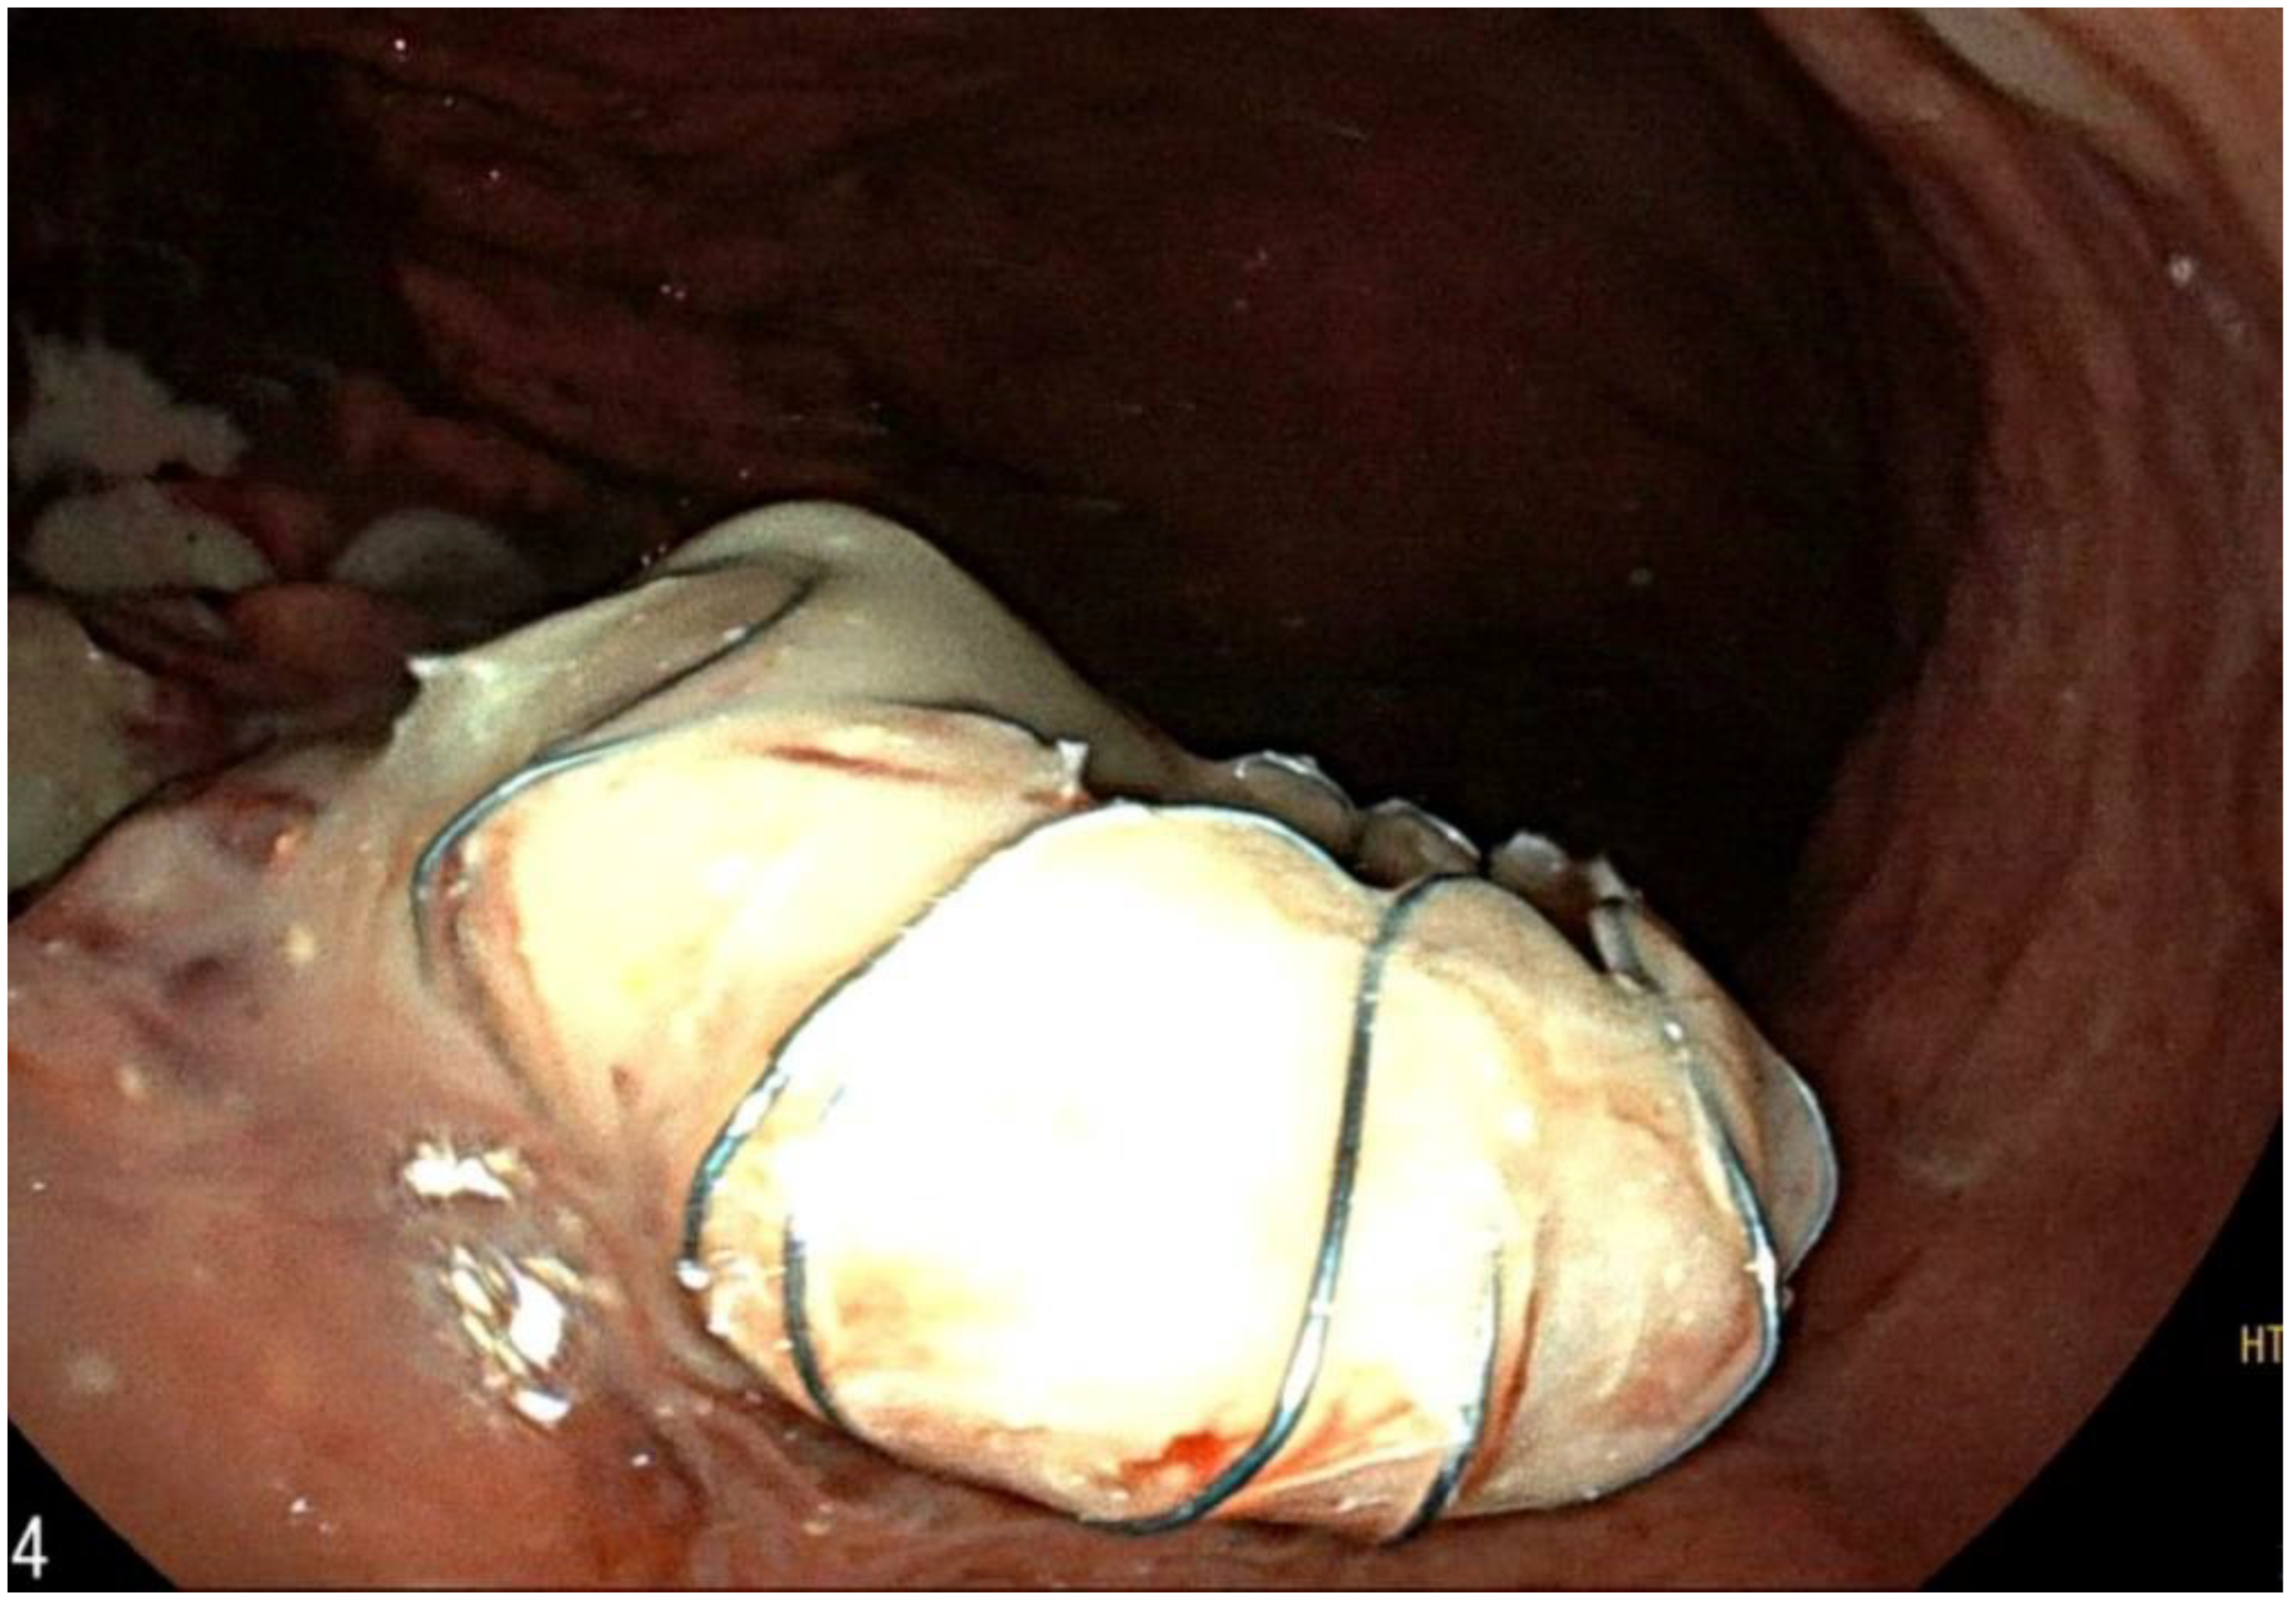

2. Case Report